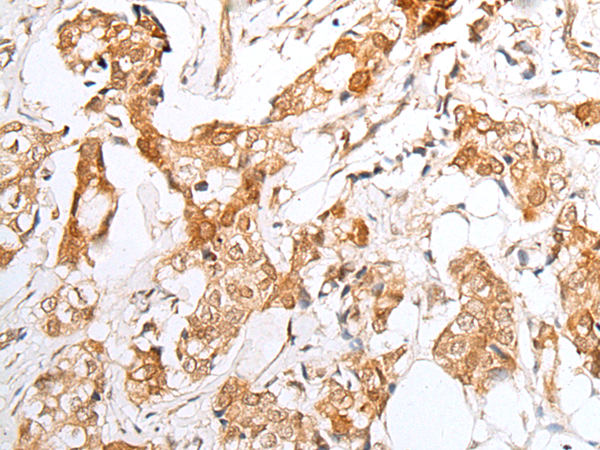

分类: 科研抗体货号: P05816别名: STMP; IPCA1; PUMPCn; STAMP1; PCANAP1应用: WB,IHC反应种属: Human, Mouse, Rat